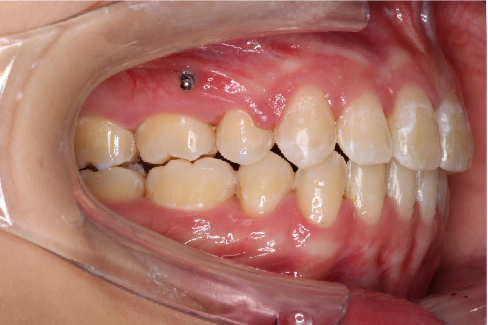

2018.11.14  术后磨牙尖牙I类关系,中线齐,覆合,覆盖正常

Post-TXPRE-TXPost-TXNormFMIA°47°57.555.0SNA°77.7°76.883.0SNB°70.2°73.780.0ANB°7.5°3.13.0FMA° 29.828.026PFH/AFH70.5°65.970Z Angle°50.3°64.477U1-FH113.0103.7110.0 IMPA°103.291.197.0U Lip tos’ line6.3 mm3.25.0L Lip to s’ line3.9 mm1.03.0OP-FH1212.615

宏观评价:面部对称,面下三分一比例协调,上下唇凸度正常,上颌牙列内收转矩控制良好,下颌后缩改善,颏唇沟变得更加柔和,术后达到基本直面型。

迷你观评价:上下牙齿中线与面中线对齐,笑弧协调,微笑时牙龈暴露量正常,微笑时横向正常,左右唇基本对称。

微观评价:牙齿整齐,咬合关系良好,上下前牙转矩及突度控制良好,磨牙关系I类,尖窝咬合关系良好,OB,OJ正常。